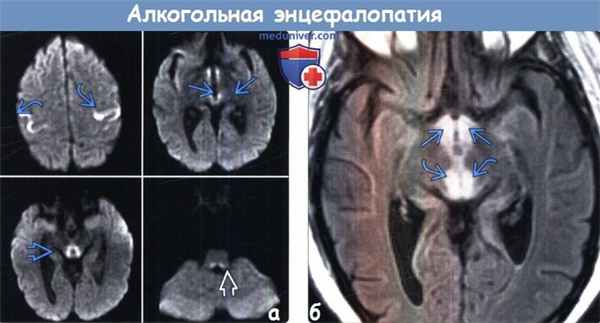

(а) МРТ, ДВИ, аксиальный срез: у пациента с острой энцефалопатией Вернике отмечается ограничение диффузии в области перироландовой коры, заднемедиальных отделах таламусов, в центральном сером веществе и дорсальных отделах продолговатого мозга.

(б) MPT, FLAIR, аксиальный срез: у этого же пациента наблюдается повышение интенсивности сигнала от дорсомедиальных отделов таламусов, а также от сосцевидных тел. Дефицит тиамина является причиной развития острой энцефалопатии Вернике.